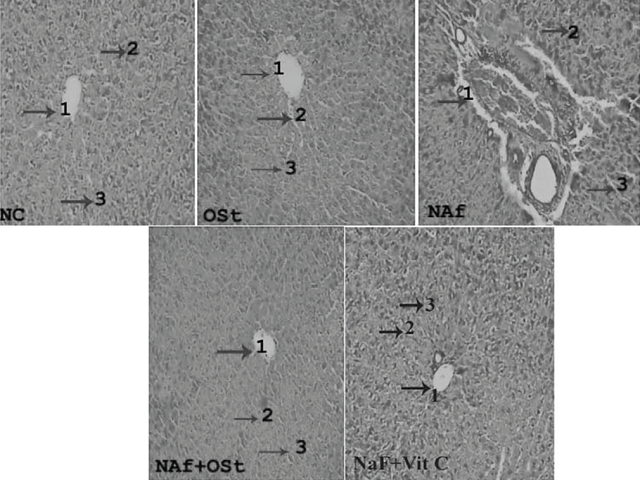

Background: Ocimum sanctum (OS) Linn. commonly known as Holy Basil or Tulsi is an Ayurvedic herb of India. The culinary, medicinal, and industrial importance of this plant led to explore its chemical and pharmacological properties. Objective: The present study was carried out to know the anti-oxidant activity of carvacrol bioactive compound of OS in sodium fluoride (NaF) rats and free-radical scavenging activities of OS. Materials and Methods: Superoxide dismutase (SOD), catalase (CAT), glutathione peroxidase (GPx), glutathione reductase (GR), glutathione (GSH), GSH-s-transferase (GST), malonaldehyde (MDA), alanine aminotransferase (AAT), aspartate aminotransferase (AST), alkaline phosphatase (ALKP), calcium (Ca), and phosphorus (P4) levels are estimated in all experimental groups. 2,2-Diphenyl-1-picrylhydrazyl (DPPH), hydrogen peroxide (H2O2), and hydroxyl radical activities are analyzed in the ethanolic extract of OS. Results: SOD, CAT, GPx, GR, GSH, activities, and Ca levels depleted and GST, MDA, AAT, AST, ALKP, and P4 levels elevated in NaF intoxicated rats. Whereas carvacrol supplementation normalized all the antioxidant enzymes and hepatic markers in NaF toxicity rats. DPPH, H2O2, and hydroxyl radical of OS showed potent free-radical scavenging activities. In addition, histopathological studies also prove that carvacrol protected the liver tissue from fluoride toxicity in rats. Conclusion: The present study revealed that carvacrol of OS modulated the antioxidant enzymes and hepatic stress markers in NaF rats. Our research study will be helpful in the development of new active principle and nutraceuticals in the area of drug resistance and therapeutic compounds against disease vectors.